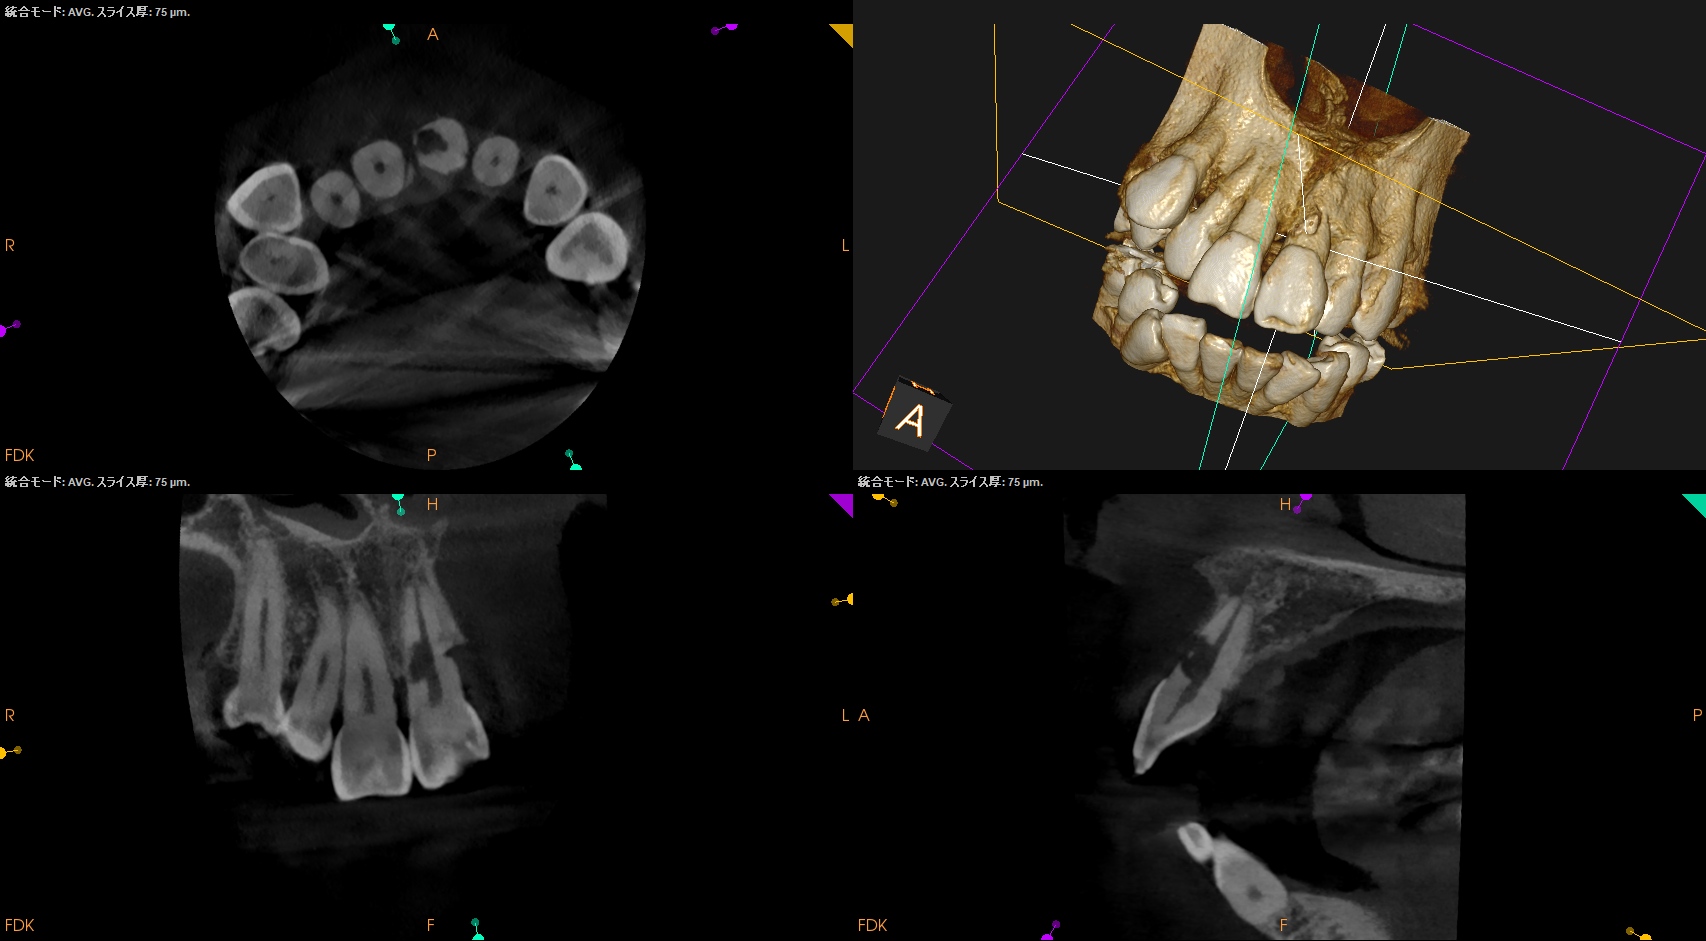

また、CBCTによればそのRIL(Radiographic Instrumentation Length)は23.4mmであるということがわかる。

そこから1mm引いた22.4mm程度が作業長だろう。

このことからもCBCTがなくては治療計画も立てられないということわかるだろう。

まず術前には緑のキシロカインは必須だ。

が、止血しても

外部吸収のRepairを行うときに根管までも封鎖してしまう可能性があるのでそこをどう処理するか?が重要だが、このCBCTの絵からはラバーダム防湿しての根管治療はほぼ無理である。

ということはそういう局面になった場合、唾液が極力入らないような環境で処置しなければらないということわかる。